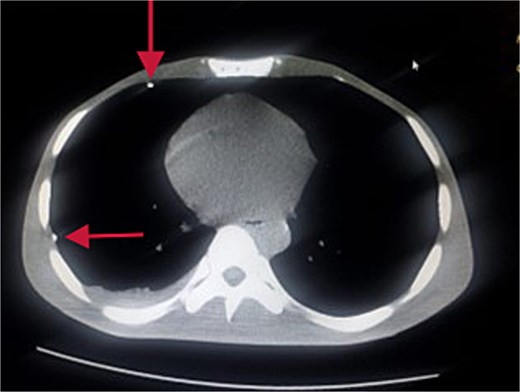

Further evaluation with chest ultrasound and computed tomography (CT) thorax, performed 48 h later, confirmed the guide wire’s position (Figs 3 and 4). The imaging studies demonstrated that the tail end of the guide wire was lodged in the right subclavian vein, while the remainder was situated in the pleural space of the right hemithorax. Notably, the guide wire was in contact with the 7th rib along the anterior and mid-axillary line. Additionally, a moderate right hemothorax had developed.